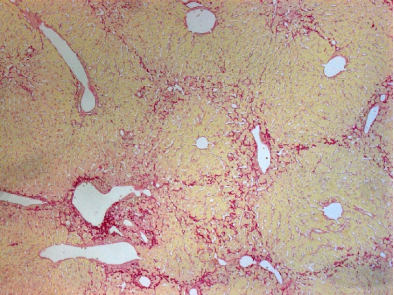

CCl4诱导性肝硬化模型

CCl4是最常用于CM 诱导的化学物质,CCl4进入机体后,首先经肝细胞微粒体细胞色素P450激活生成活性三氯甲基,CCl4通过攻击肝细胞膜的磷脂引起脂质过氧化从而破坏膜性结构,CC1 一还可与蛋白质共价结合,损害线粒体导致还原性辅酶A(NADH)和三磷酸腺苷(ATP)在肝内生成减少,进而抑制脂肪酸氧化和三羧酸循环。此外,由于内质网受损可导致脂蛋白合成障碍,使三酰甘油和脂肪酸在肝细胞内蓄积,形成脂肪变性。因此,低浓度的CC1 反复应用,可使大鼠的肝组织受到损害-修复-损害的循环破坏作用.最终导致肝纤维化及肝硬化的发生。

一般采用30%-60%CCl4油剂,0.1-0.3ml/100g体重,皮下注射,每周2次,也可以用腹腔注射、灌胃或蒸汽吸入等途径给药。改方法试验周期较长,肝硬化一般在12-15周形成。动物死亡率也较高,通常在30%-40%。降低CCl4的浓度,可减少动物死亡率。腹腔注射肝硬化形成相对较快,一般8周即可,但动物死亡率较高。